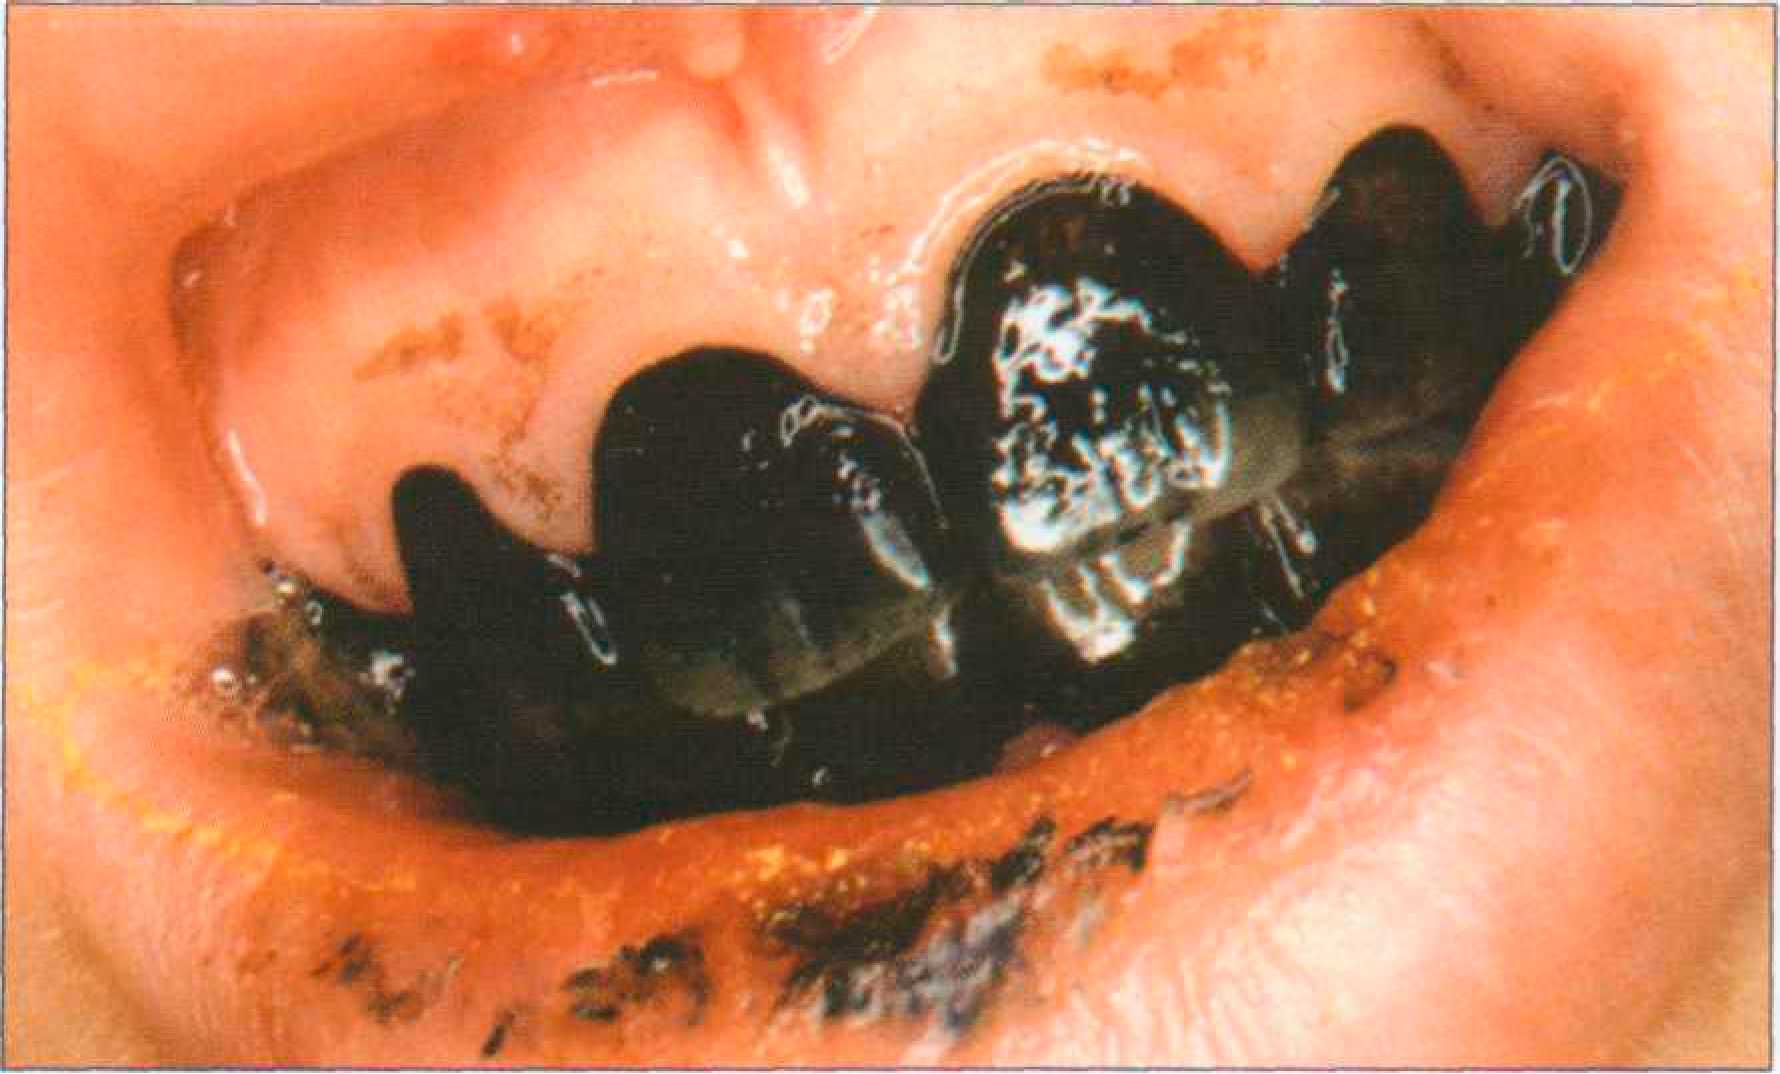

Благодаря высокой пористости участки деминерализации могут пигментироваться, приобретая желтоватую, бурую, коричневую окраску в зависимости от воздействующего красителя. Пары брома и йода окрашивают пришеечные области зубов в желтоватый цвет. Коричнево-черный налет на зубах появляется у лиц, занятых обработкой металлов (марганец, железо, никель). Хроническое отравление ртутью, сулемой, свинцом приводит к диффузному окрашиванию зубов различной интенсивности от серого до черного или от желтого до коричневого цвета. Особо следует остановиться на пигментации зубов у курильщиков (экзогенное, системное, поверхностное и глубокое окрашивание). Наиболее характерно образование темно-коричневого, почти черного налета вдоль шеек зубов, а также на тех поверхностях, которые не участвуют в жевании и плохо очищаются. Образованию «налета курильщиков» способствует плохая гигиена полости рта (рис. 173 а, б).

Рис. 173. Выраженная пигментация язычной поверхности резцов: налет "курильщика" — а; состояние после профессиональной гигиены — 6 Сходная окраска, которую можно отнести к воздействию пищевых пигментов, однако менее интенсивная и менее стойкая, чем у курильщиков, наблюдается у любителей крепкого чая и кофе. Содержание в питьевой воде железа может вызвать устойчивую синеватую окраску зубов. Выраженная пигментация органических покровов зуба может появляться в результате воздействия хлоргексидина, который назначают для полосканий (рис. 174).